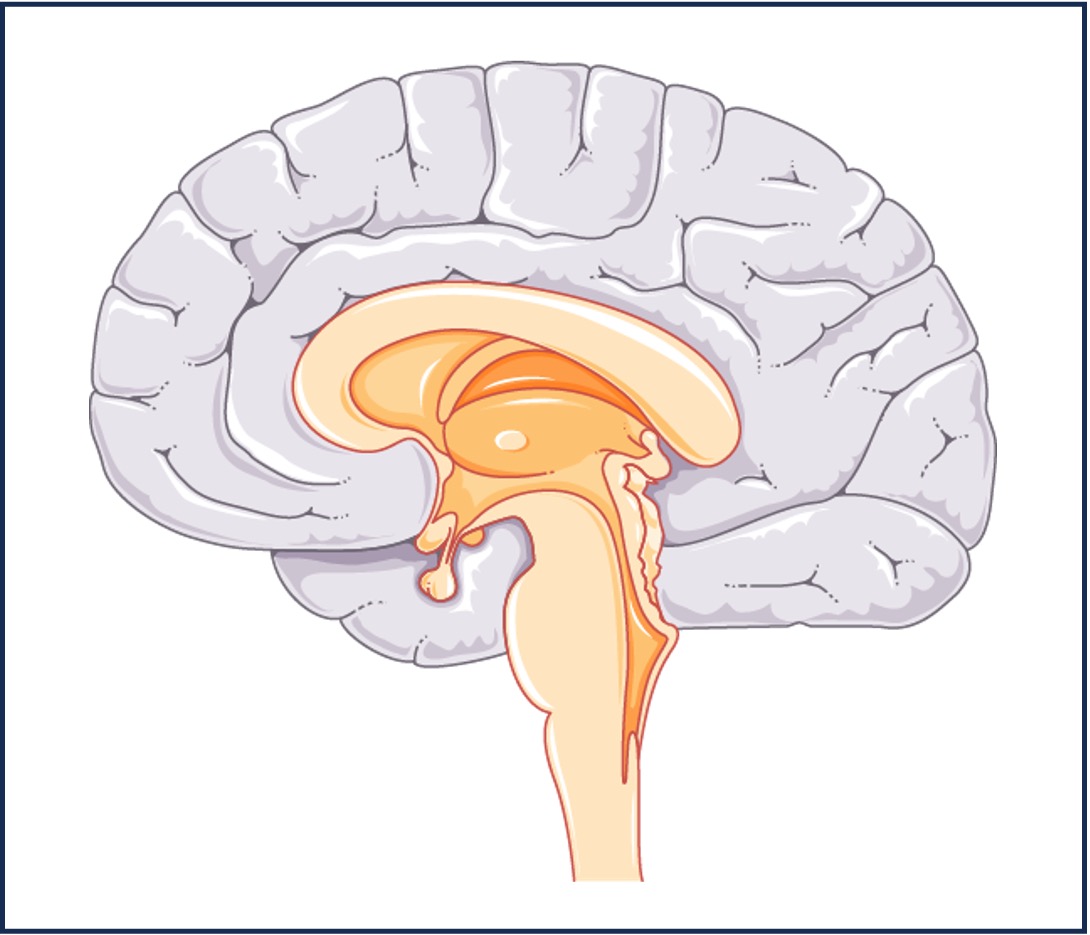

Puberty is triggered by the release of gonadotropin releasing hormone (GnRH) from the hypothalamus of the brain

-

GnRH travels in the bloodstream to the pituitary gland and triggers the secretion of FSH and LH from the anterior lobe

-